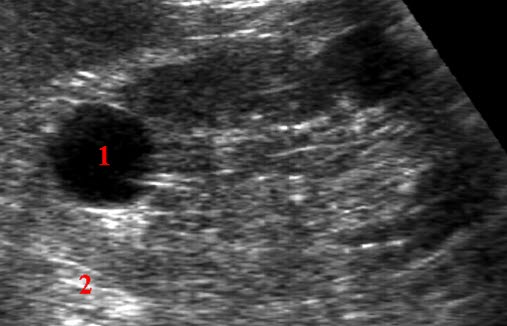

Lavekkogen (mørk), velavgrenset, homogen rund cyste (1) i øvre nyrepol. Bak cysten er det ekkoforsterkning (lysere område) (2)